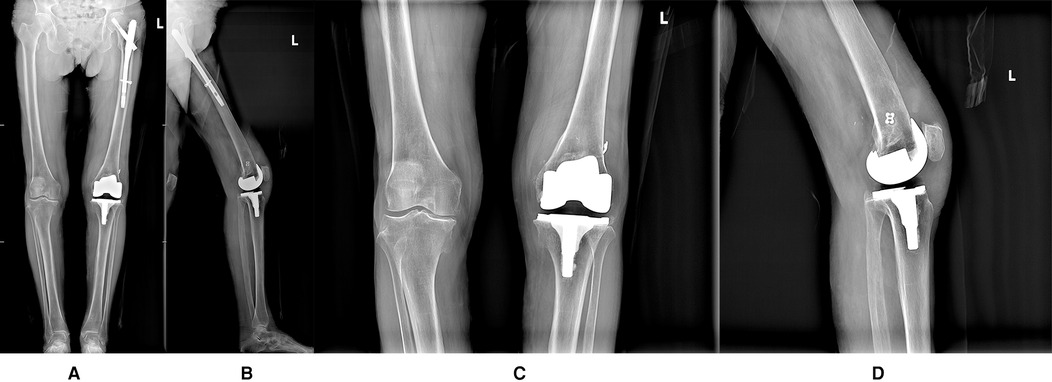

Figure 3

Figure10-13 display four postoperative radiographs to show the position of prosthesis and patella, and the lower limb force line is ideal.

Figure 3. (A) Full-length frontal radiograph of the lower limb (Postoperative radiograph); (B) Full-length lateral radiograph of the lower limb (Postoperative radiograph); (C) Frontal radiograph of left knee joint (Postoperative radiograph); (D) Lateral radiograph of left knee joint (Postoperative radiograph).

Postoperative rehabilitation

The affected limb was placed in a hinged knee brace locked in extension. Ankle pumps and quadriceps strengthening exercises were initiated on postoperative day 2. Knee flexion exercises commenced 1 week postoperatively, with ambulation assisted by a walker and maintaining straight leg raises. The surgical incision healed by first intention, and sutures were removed two weeks postoperatively.At the one-month follow-up, the patient continues with flexion-extension exercises and quadriceps strengthening exercises. The patient reflected subjective satisfaction, ambulating with walker assistance and experiencing mild pain (with a VAS score of 3) after walking, which resolved with rest. The KSS clinical score was 85, functional score was 60, OKS score was 28. The left knee joint was stable with active flexion-extension range of 0–90°. By the 2-month follow-up, the patient expressed high subjective satisfaction, demonstrating normal gait without significant pain (with a VAS score of 1). The KSS clinical score was 90, functional score was 80, OKS score was 15. The left knee remained stable with active flexion-extension range of 0–100° (refer to Supplementary Video S3). The most recent follow-up, conducted seven months postoperatively, revealed no complications, including prosthetic loosening, periprosthetic infection, or lower extremity thrombosis. The patient expressed high satisfaction with the surgical outcome.The patient demonstrated unrestricted walking ability, reported no significant pain in the affected limb (with a VAS score of 0), and exhibited good functional performance during left knee flexion-extension without notable patellar displacement. The KSS clinical score was 93, functional score was 90, OKS score was 12. A follow-up radiograph confirmed that the prosthesis's position is optimal (Figures 4A–D).

Figure 4

Figure 14-17 presents four radiographs taken at the 7-month postoperative follow-up to shhow the position of prosthesis and patella, and the lower limb force line is ideal.

Figure 4. (A) Full-length frontal radiograph of the lower limb (The 7-month postoperative follow-up radiograph); (B) Full-length lateral radiograph of the lower limb (The 7-month postoperative follow-up radiograph); (C) Frontal radiograph of left knee joint (The 7-month postoperative follow-up radiograph); (D) Lateral radiograph of left knee joint (The 7-month postoperative follow-up radiograph).